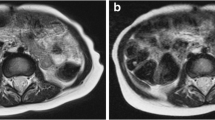

Neonates

We performed a sub-analysis of the small number of neonatal exams, and representative images are shown in Fig. 5. The overall imaging score for the feed-and-swaddle examinations using radial T2-W sequences was not statistically different from either the total breath-hold group (encompassing all ages) (T2-W SSFSE mean of 3.3 compared with radial T2-W mean of 3.8, P=0.06) or an age-matched group of breath-held neonates (P=0.15). Similarly, there was no difference in the overall imaging scores in the feed-and-swaddle contrast-enhanced T1-W sequences using 3-D radial imaging from the breath-held T1-W sequence (T1 mDixon mean of 3.5 compared with 3-D radial mean of 3.8, P=0.20) or the age-matched breath-held neonates (T1 mDixon mean of 2.9 compared with 3-D radial mean of 3.8, P=0.07). Motion artifact scores across the age-matched groups were also not significantly different for the T2-W sequences (T2-W SSFSE mean of 4.0 compared with radial T2-W mean of 3.6, P=0.30) or for the contrast-enhanced T1-W sequences (T1-W mDixon mean of 4.3 compared with 3-D radial mean of 4.2, P=0.70).

Neonatal imaging examples and their scores. a Free-breathing axial radial T2-W fat-saturated MRI performed with swaddling in a 9-day-old boy with a right adrenal mass cyst (C). The overall imaging score for the T2-W sequence was 3.8. b Breath-hold axial T2-W single-shot fast spin-echo (SSFSE) MRI performed with general anesthesia in a 1-month-old boy with vascular malformation (VM), with an imaging score for the T2 sequence of 3.4. c Axial contrast-enhanced T1-W 3-D radial image obtained with intravenous sedation in same infant as (a), with an overall imaging score of 3.4. d Breath-held axial T1-W modified Dixon image obtained with general anesthesia in same infant as (b), with an overall imaging score of 4.0